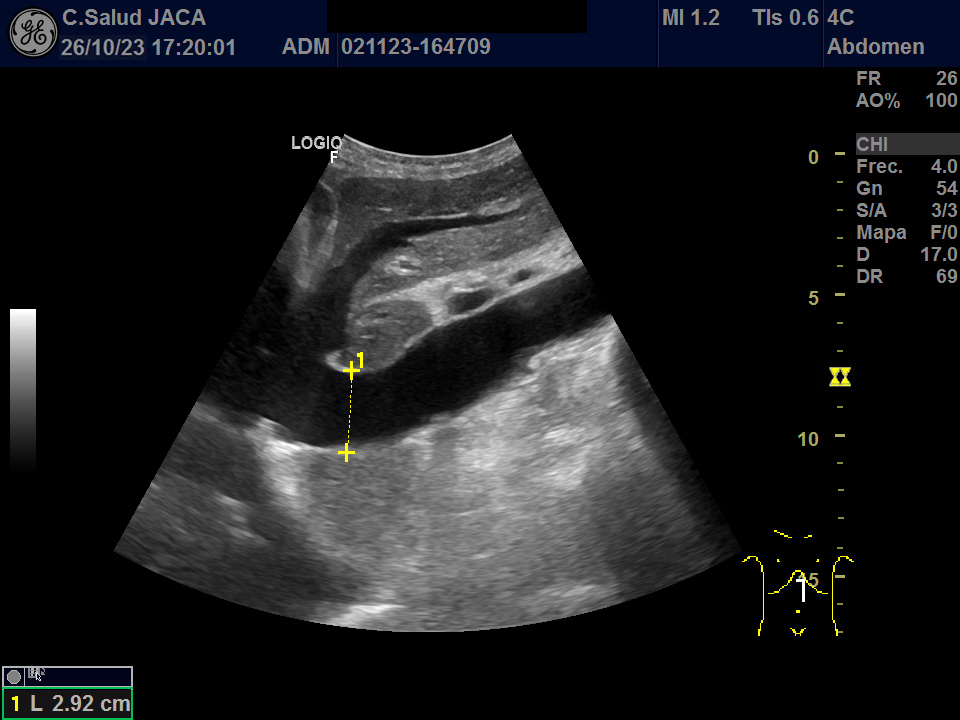

Presentamos las ilustrativas imágenes ecográficas obtenidas con sonda convex en la consulta de su Médico de Familia, que muestran derrame pleural y pericárdico, gran dilatación de ambas aurículas (ventana subxifoidea), ascitis, engrosamiento de 30 mm de la cava a su entrada en la aurícula derecha, que no se modifica con la inspiración, y congestión igualmente de las venas suprahepáticas.